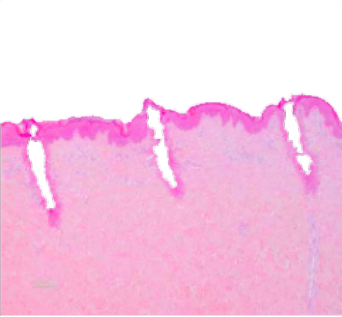

This energy is delivered through a narrow range of wavelengths, elevating the temperature in the targeted area, resulting in tissue evaporation or ablation. Ablative lasers effectively treat a broad range of skin conditions by removing all or only parts of the skin in a fractional manner. The body’s natural healing processes then drive the production of new elastin and collagen fibers, which help replace damaged skin with new and healthy tissue.

CO2 lasers produce light at a 10,600nm wavelength, which is absorbed by water molecules in the tissue. The laser energy heats up the water until it reaches a boiling point, causing the evaporation of the affected tissue. Some of the heat is absorbed by the tissue adjacent to the ablated target area, causing tissue coagulation which induces hemostasis (the cessation of bleeding) as well as thermal stimulation of deep skin layers, which induces fibroblast stimulation and neocollagenesis (the formation of new collagen).

The laser beam can also be transmitted through a scanner which is a device used to further control the delivery of energy. The scanner regulates the configuration of energy delivered onto the skin, which can range from covering the entire treatment area or just a fraction of it, leaving some areas of untreated skin that drive faster recovery (“fractional ablation”). The overall effect of ablation and coagulation, either full or fractional, is the removal of damaged skin and the stimulation of the body to replace it with newer, younger, and vibrant skin.